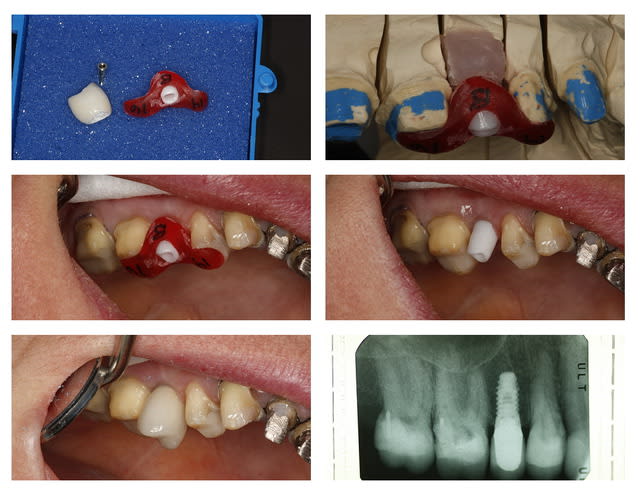

c'est posé

aucune vis

prothèse scellée

comme les autres ce sont des cônes morses, uniquement impactés

pas de scellement

tu positionnes, un "coup" de maillet et c'est mis.

j'ai juste un RX avec "cap" de cicat en place et une photo avant la pose des piliers

voili voilou, avant après et les tissus mous

le blanchiment du bas est prévu, un de mes associés le fera

je mets donc une photo de g à d

1)le "cap" de cicatrisation, avec son embout, pour le mettre et le frapper

2)le transfert qui lui est indexé

3)un faux moignon droit indexé fixe que tu peux tailler en bouche

4)un FM avec une indexation par hexagone non solidaire avec elle aussi un cône morse, ce qui permet un positionnement à 360°.